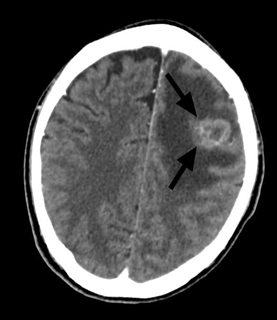

Figure 5 CT scan of the brain showing a solitary intra-axial lesion at grey white matter junction of the left frontal region (black arrow) with thick nodular ring enhancement pattern post contrast. It is associated with extensive white matter edema.

A 59 years old gentleman who was an ex-chronic smoker (40 pack-years) was referred to our centre for a huge left breast mass. On further history, the patient claimed that the left breast swelling has been there for the past one year and he never seek any medical treatment. While in the ward patient developed generalized tonic-clonic seizure (GTC) for six episodes, aborted by intravenous Phenytoin. An urgent brain computed tomography (CT) was performed and a left frontal intra-axial space-occupying lesion was found. Clinically, the left breast swelling was irregular in shape, measuring about (18x5) cm, hard, non-tender and fixed to the underlying structures. There were left axillary lymph nodes palpable. A TRU-CUT biopsy of the left breast mass was performed and histopathology results came out as Invasive breast carcinoma of no special type (NST).Contrasted tomography (CECT) of the thorax was performed for the staging purpose and was reported as the presence of lobulated heterogeneously enhanced mass occupying the whole left breast measuring (11.1x4.7x9.2) cm with an erosion of the left anterior end of second to fourth lateral surfaces of the ribs. Also, there were multiple enhancing axillary lymph nodes bilaterally, at the pre-tracheal, para-tracheal, sub-carina and the presence of lung nodule in the superior segment. There was metastatic lesion seen on the left adrenal gland measuring (3.7x2.9x3.5) cm as well. The patient was staged as T4N1M1. No surgery was done as patient deteriorated and succumbed to death due to Pulmonary Embolism (PE) on day eleventh of admission (Figure 3–5).